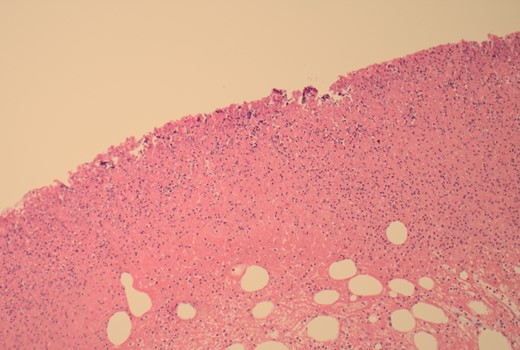

The patient was taken to the theatre for an emergency laparotomy. Intraoperative findings were of high-grade SBO, secondary to terminal ileal intussusception. The involved small bowel was viable with no perforation. The intussusception was reduced. Nidus was an intraluminal polypoid lesion. A small bowel resection and a primary, double-layered hand-sewn anastomosis were performed. A specimen was sent for histology. Histology confirmed an ulcerated benign submucosal lipoma (45 × 30 × 22 mm) as the cause (Figs 4–7).

100× magnification showing the ulcerated surface of the lipoma which is covered by fibrin and neutrophils. The clear cystic spaces below this are the residual fat cells.

100× magnification of the lipoma illustrating the adipocytes which show cytoplasmic distention by optically clear fat.